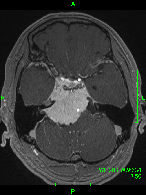

症例1) 65歳男性、頭蓋底部巨大髄膜腫、外科手術のみ

<画像所見>

巨大脳腫瘍を認める。

錐体斜台部巨大髄膜腫を認め、

神経や血管を巻き込んでいる。